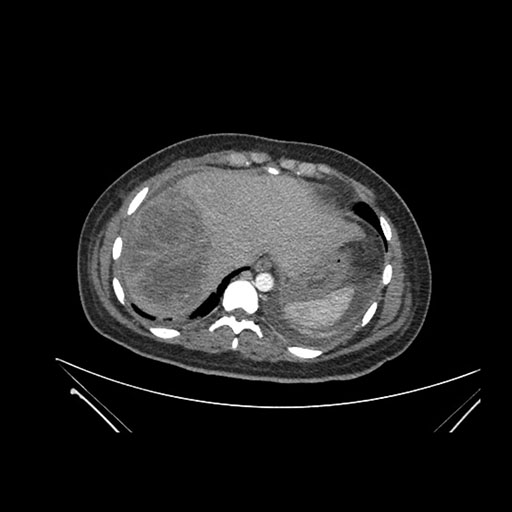

Axial Venous